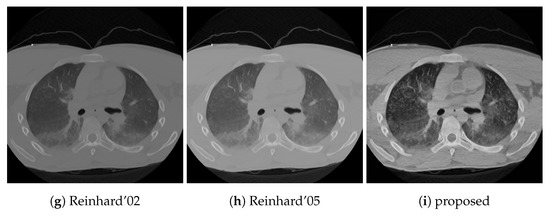

The results of our proposed algorithm are demonstrated in two ways. First, it has been compared to 8 different tone mapping operators, Ferradans [24], Drago [22], Durand [19], Fattal [21], Mantiuk ’06 [38] and ’08 [25], and Reinhard ’02 [20] and ’05 [23], using two post-mortem CT examples, a head and a chest CT. Second, the effects of changes of the algorithm parameters are depicted in two image montages, using the above-mentioned chest CT and a color photo of a ship, in Figure 4. The purpose of the ship image is to demonstrate that the algorithm is not specific to CT images. The image is an RGB image which was transformed to HSV color space [9], and the V component was processed using 256 discretization levels.

Next to the structural similarity, gradient magnitude and image entropy are also reported. These three quantitative results are presented in Table 2, while the tone mapped images are shown in Figure 5 and Figure 6.

The effect of the two control parameters, the exponent of the power-law, and the contrast limit is visualized in Figure 7 and Figure 8. Faster decreasing weights further enhance the local features, including noise. The contrast limit from CLAHE effectively regulates this issue.

Figure 7.

The effect of the weighting function and clipping. Rows from top to bottom have a = 0.7, 1.0, 1.5, 2.0, respectively, and the clip limits in the columns from left to right are 1, 5, 10 and 20, using units where N is the number of histogram bins.